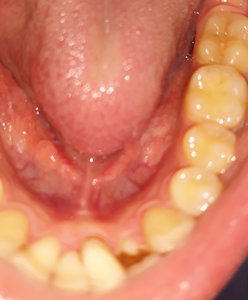

Второй вопрос: Мне вылечили от кариеса семнадцатый и двадцать шестой зубы. Лечение производилось от двух до трех недель назад. До этого жевать было удобно, как твердую, так и мягкую пищу. Сейчас есть мягкую пищу удобно и комфортно, а твердую - не очень. Болей нет, но ощущения не очень приятные. В районе семнадцатого и двадцать шестого, ощущается некий дискомфорт.

С чем это может быть связано?

На снимке в области семнадцатого и двадцать шестого зуба, под пломбой, наблюдается полость, которая неграмотно препарирована перед установкой пломбы, чувствительность и некий дискомфорт при надкусывании или пережевывании твердой пищи связано именно с этим. Что касается шестнадцатого зуба, я считаю, что полость имеется, но все-таки необходим еще и очный прием.